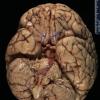

Mucormycosis - Zygomycosis